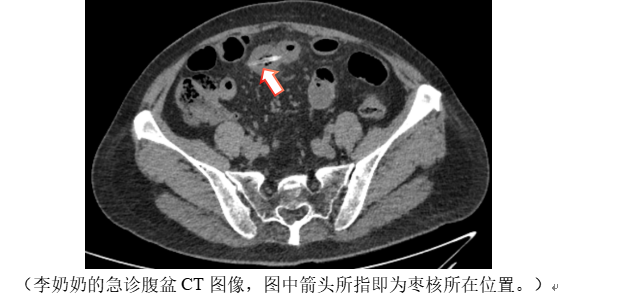

2023年冬天,笔者夜班时遇到因腹痛就诊于急诊的70岁李奶奶,在她的腹盆CT中,找到一枚卡顿于回肠的尖锐异物,此时异物已刺穿肠壁,形成直径约0.5厘米的破口,并且因肠道内容物的渗漏而引发了腹膜炎,若再晚几小时,不排除因感染加重而产生更为严重的后果。外科医生经腹腔镜手术取出枣核并修补肠道,老人家才转危为安。